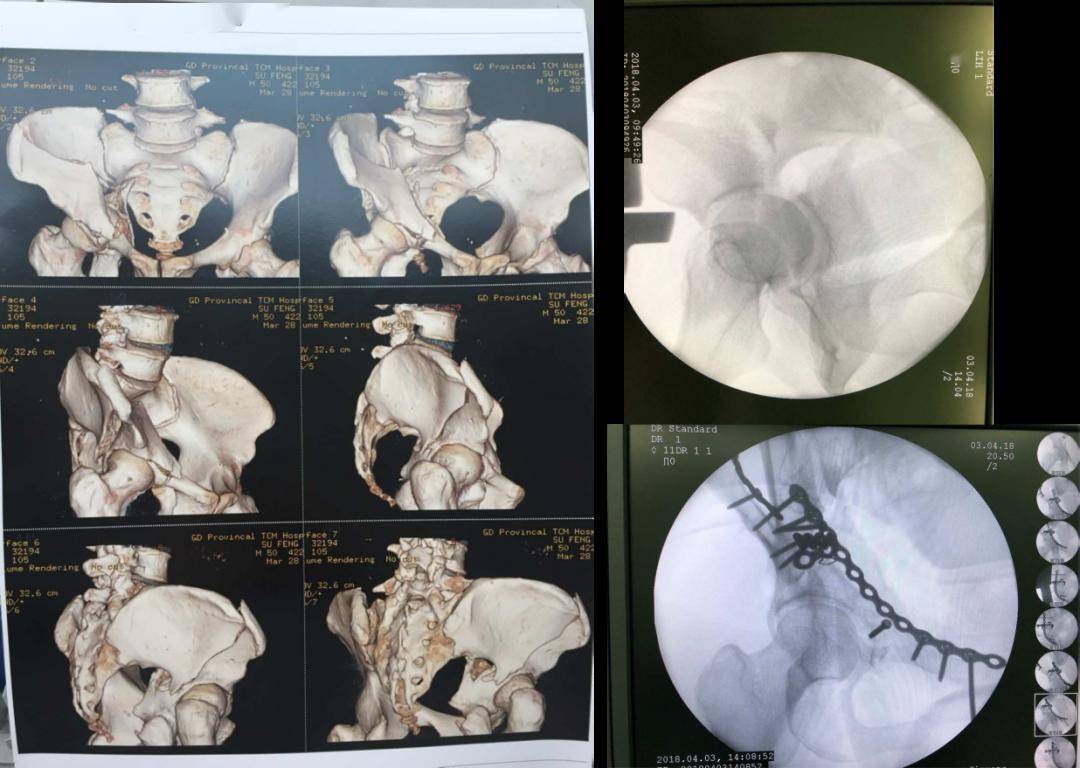

入院后,经运动创伤科、内分泌科、心血管科等多学科会诊,控制血糖、治疗酮症、介入防血栓、心血管科调整抗凝方案等等综合处理,张奶奶内科病情稳定,此时髋臼骨折已经是一个多月的陈旧性骨折了。

此时告知患者以后卧床或者坐轮椅,这是风险较小,责任较少,大多数人都不会质疑的选择。但看着患者殷切的眼神与家属的期待,科室江涛主任团队决定接下这个“烫手山芋”。江涛主任带领治疗团队为张奶奶制定了详细的手术方案和术前准备,为术中可能的并发症和困难均做好了预案。

手术非常顺利,术后第四天,张奶奶就可以坐在床边活动,术后2个月已能重新站立练习行走了。患者及家属终于摆脱了长期坐轮椅、卧床失能的噩梦。